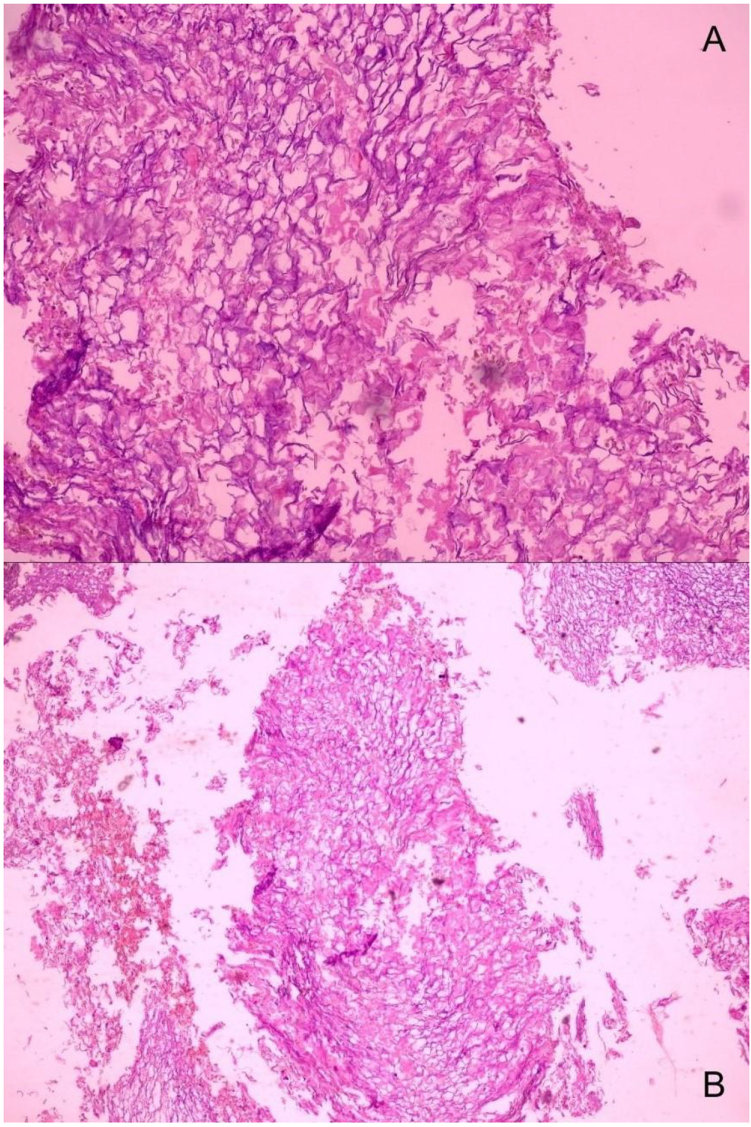

乳腺超声(图1):右乳可见边界清晰的不均质实性结节,内部见线状强回声呈“洋葱环”样排列,彩色多普勒血流显像无内部血流信号。

图 1 乳腺超声(右乳)